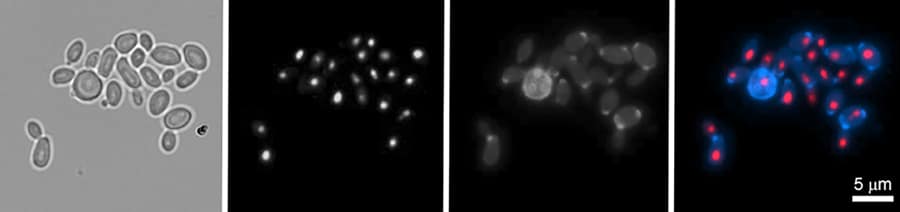

另外,在某些基因毒性条件下,许多C. Auris.菌株能够形成称为假海豚的长丝。虽然数据不足以证实假鼠在毒力中的作用C. Auris.在其他真菌中,丝状生长已被证明在寄主-病原体附着和疾病发展中发挥重要作用。与具有可塑性和适应性的基因组相结合C. Auris.,这种能力可以允许临床分离物在发病机制过程中利用丝状生长。

而C. Auris.已经证明自己是一个可怕的和“神秘的”有机体,Lorenz和他的团队找到了一种潜在的反击方法——至少在临床上是这样。然而,研究人员使用的不是一种抗真菌药物,而是另一种真菌。当与C. Auris.,捕食性酵母,酵母属schoenii它使用特殊的矛状结构攻击并杀死狱友。在六个小时之内,S. Schoenii.已被淘汰了34%C. Auris.,虽然几乎没有C. Auris.细胞在单独培养时死亡。重要的是,耐药形式C. Auris.仍然容易受到捕食者的影响。结果制作S. Schoenii.这是一种很有前途的生物防治方法。